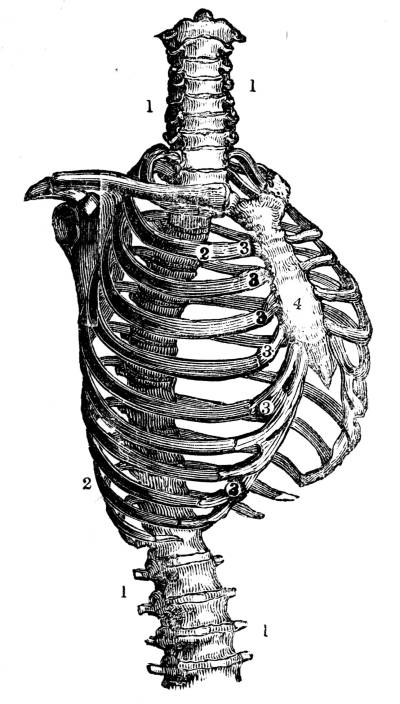

Fig. CXLI.—

View of the osseous portion of the Thorax.

1. Spinal column. 2. Ribs. 3. Cartilages of ribs. 4.

Sternum.

377. The osseous portion of the thorax, which

has been fully described (69 et seq.), consists of

the spinal column (fig. CXLI. 1), the ribs with their

cartilages (fig. CXLI. 2, 3), and the sternum (fig.

CXLI. 4). The soft portion of the thorax consists of

380. The ribs form a series of moveable arches,

the convexity of the arches being outwards, and53

the whole being disposed in an oblique direction

(fig. CXLI. 2). The first rib springs from the ver54tebral

column at nearly a right angle (fig. CXLI.

2); the acuteness of this angle increases in succession

as the ribs descend from the first to the

last (fig. CXLI. 2); in this manner each rib is

inclined obliquely outwards and downwards, and

the obliquity thus given to the general direction of

the ribs augments progressively from above downwards

(fig. CXLI. 2).

381. In consequence of this conformation and

arrangement of the ribs, every degree of motion

which is communicated to them, necessarily influences

the capacity of the space they enclose.

If they are moved upwards they must enlarge that

space at the sides, because the intervals between

each other will be increased (fig. CXLI. 2);

and from behind forwards, because the distance

between the spinal column and the sternum (the

sternum being protruded forwards with their cartilaginous

extremities) (fig. CXLI. 3, 4), will be increased.

If, on the other hand, they are moved

downwards, the capacity of the thorax will be proportionally

diminished in every direction (fig.

CXLI. ).